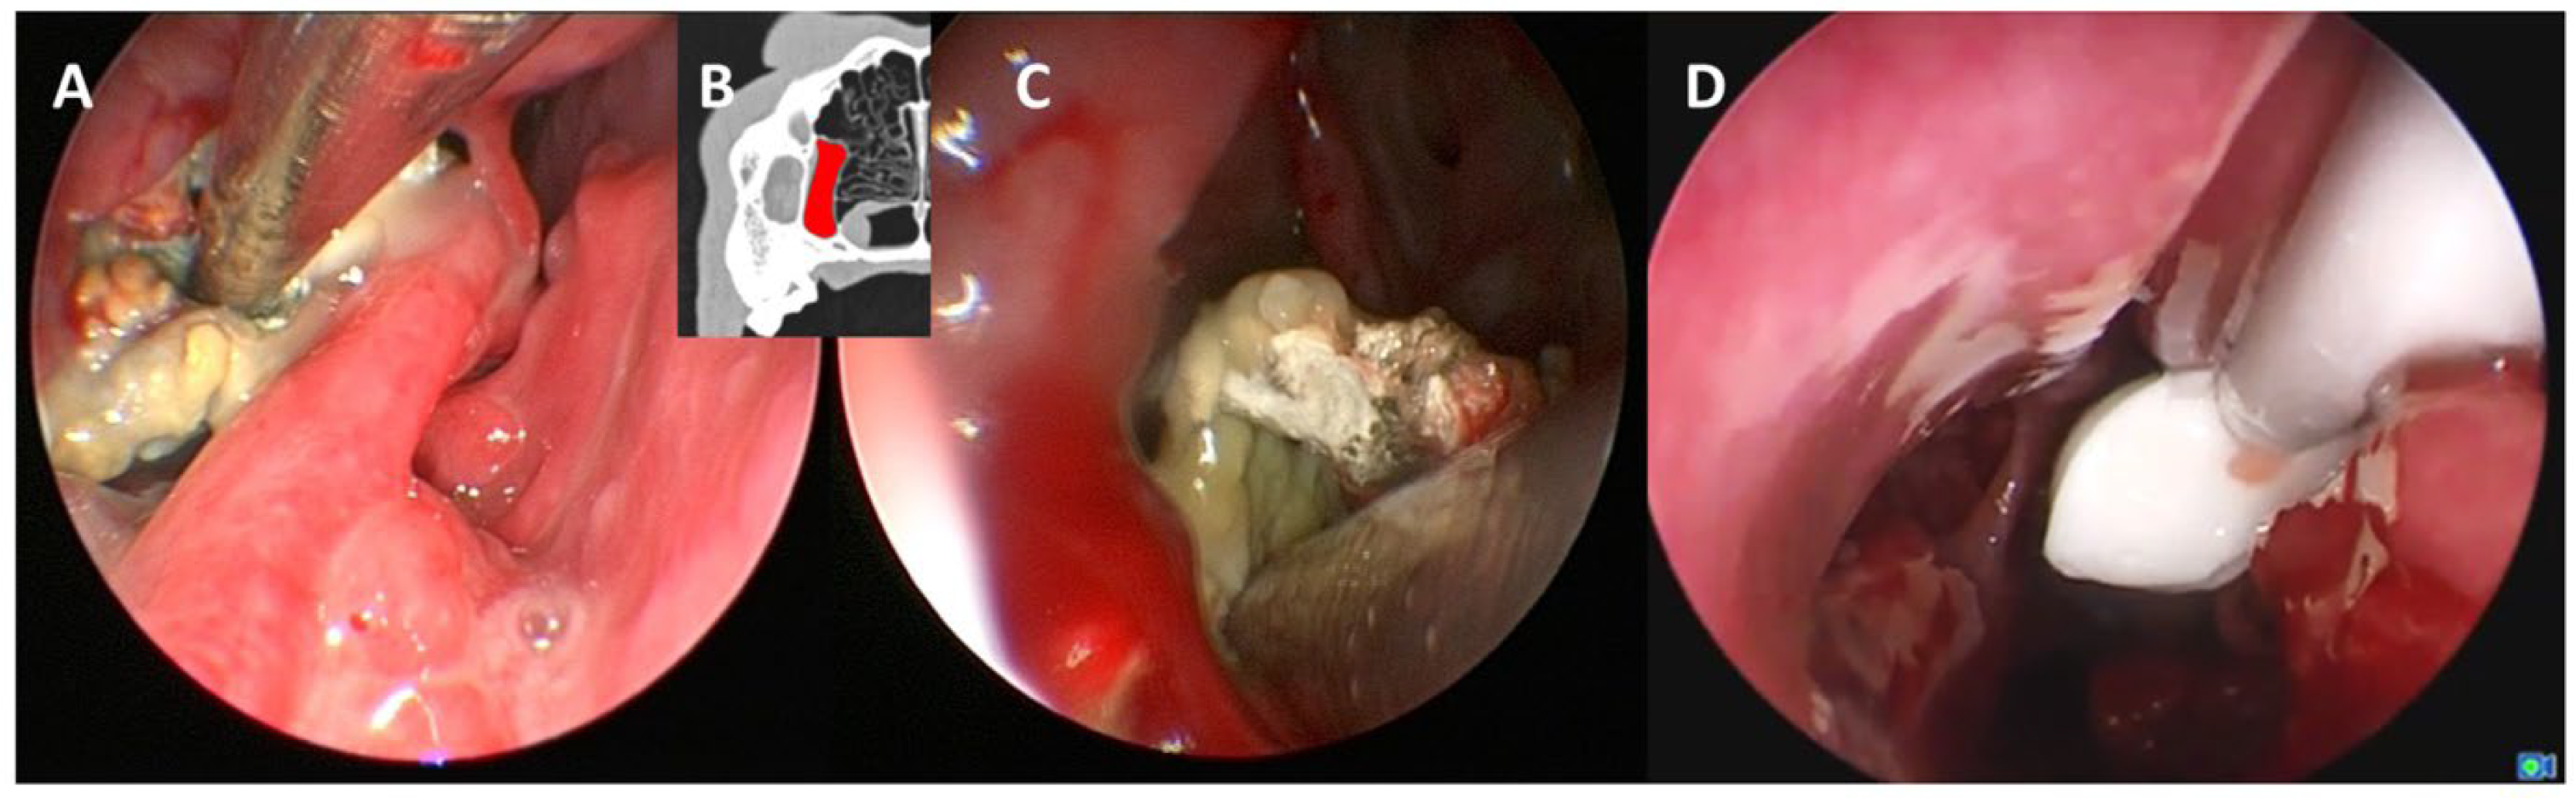

The dogs were placed in sternal recumbency with maxillary fixation caudal to the canines; the mandible was left unrestrained. The following endoscopically obtained findings were documented: changes in the nasal mucosa of the turbinates and nasal septum, fluid accumulation, localization of mycotic plaques or granulomas, a pathologically open entrance to the frontal sinus, and evidence of a foreign body or other pathology. A mycotic plaque or granuloma was characterized by a firm, yellowish-white mass with a mold-like appearance on the surface (Figure 2).

As a result, evaluation of the frontal sinus was initially performed using the cross-sectional images in the included dogs with aspergillosis. During subsequent rhinoscopy, the frontal sinus was assessed for content and whether the opening to the frontal sinus had already been widened due to the aspergillus infection. If alterations to the frontal sinus were detected in the cross-sectional images (e.g., fluid accumulation or bony alterations to the frontal bone), but no pathological widening was observed during rhinoscopy, endoscopic therapeutic intervention to open the frontal sinus was performed (Figure 2).

Frontal sinus granuloma and degree of opening of the frontal sinus into the nasal cavity: In 2/15 dogs (13%) with a fungal granuloma located in the frontal sinus, information regarding the width of the frontal sinus opening into the nasal cavity was not available. In 8/15 dogs (53%; 7 pA and 1 sA), direct endoscopic visualization and access to the frontal sinus were possible due to a pathologically widened frontal sinus opening. In 5/15 dogs (33%; 4 pA and 1 sA), the frontal sinus opening was not widened and was therefore inaccessible without endoscopic therapeutic intervention. In these five dogs, including one sA dog with periodontopathy and a hidden granuloma in the frontal sinus, the fungal granuloma was only detected after endonasal endoscopic trephination of the bony border of the frontal sinus (Figure 2 and Figure 7). No complications, such as major bleeding, were observed during or after the procedure of endonasal endoscopic trephination.